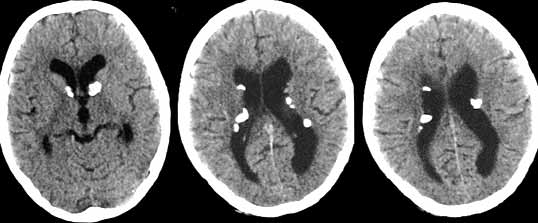

Туберозный склероз.

Рис. 1. РК-томограммы головного мозга. Визуализируются мультифокальные очаги высокой плотности, расположенные субэпиндимально.